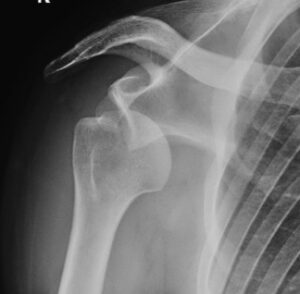

La inestabilidad de hombro, también llamada inestabilidad glenohumeral, se refiere a la pérdida de la relación normal entre el húmero y la escápula. De manera que la cabeza del húmero se sale o tiende a salirse de la cavidad glenoidea (glena), que es la parte de la escápula con la que articula el húmero.

En el caso de una luxación aguda, el diagnóstico es evidente por los síntomas antes descritos. Se confirma con una radiografía que demuestra una pérdida de la relación normal de la cabeza humeral y la escápula.

Una vez reducido el hombro, se realiza una nueva radiografía en la misma proyección que nos confirme que ha vuelto a su sitio. Más tarde se suele realizar una resonancia magnética para valorar el grado de lesiones óseas y de partes blandas, si las hubiera. Frecuentemente la resonancia mostrará las dos lesiones típicas que hemos comentado antes (Bankart y Hill-Sachs). En los casos en que el hombro se haya salido en muchas ocasiones (luxación recidivante) puede existir un defecto de hueso en la parte anterior de la glena y la lesión de Hill-Sachs suele ser más grande.